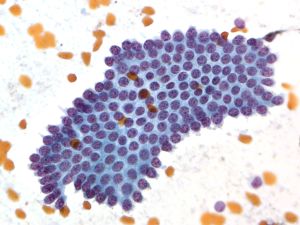

Neuroendocrine Tumor –MN07-R09706 and N13-6431

Key Cytological Features: Pancreatic Neuroendocrine Tumor

- Discohesive, single cell "solid-cellular "smear pattern

- Uniform, monotonous population of cells with plasmacytoid features

- Coarse, speckled, “salt and pepper” chromatin pattern

- Nucleoli may be prominent

- Dense, finely granular cytoplasm